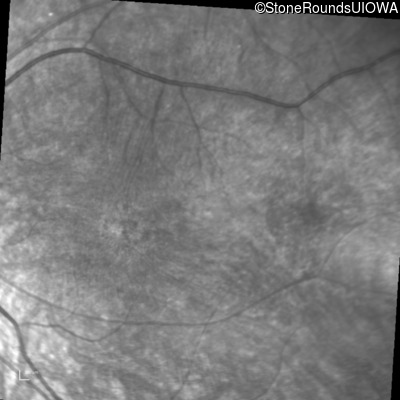

Infrared Fundus Photograph - Right - 20/100 -1 sc

Exemplar

Infrared Fundus Photograph - Left - 20/100 -2 sc